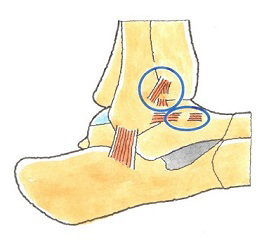

足関節は多くの靭帯などに守られ、捻挫が起こりにくいように安定性を図られていることが、上のイラス トで改めてお分かり頂けると思います。

ところが、足関節捻挫をおこし、その後これらの靭帯とりわけ前距腓靭帯や踵腓靭帯などが十分修復 されていませんと、そのことを原因として、足関節が不安定になります。さらに放置しておくと、足関節 の靭帯が付着している軟骨も損傷したり剥離したりして、変形性足関節症に至ることもあり、日常歩行に深刻な影響を及ぼします。

内返しが強制されて損傷する靭帯は、通常、外側靭帯(がいそくじんたい)です。

外側靭帯とは、前距腓靭帯(ぜんきょひじんたい)、踵腓靭帯(しょうひじんたい)、後距腓靭帯(こうきょひじんたい)の3つの靭帯を総称したものです。いずれも外くるぶしの下側に存在しています。

前距腓靭帯は、足関節外側の靭帯の中では一番前方にある靭帯です。距骨前部と腓骨を結び付けており、距骨が前に滑らないようにするはたらきをしています。厚さは約2ミリメートルです。踵腓靭帯や後距腓靭帯に比べると弱いです。

踵腓靭帯は、外くるぶしの下側やや後方にある靭帯です。踵骨と腓骨を結び付けており、距骨が内側に傾き過ぎることを防いでいます。厚さは約6ミリメートルです。 後距腓靭帯は、足部外側後方にある靭帯です。距骨後部と腓骨を結んでおり、外側靭帯の中では最も強靭な靭帯です。厚さは約6ミリメートルです。

足首捻挫が生じたというとき、足の裏が内側後方を向くような形で捻るということが多いです。

このとき、最初に強い緊張を加えられるのが前距腓靭帯です。外側靭帯の中でも特に損傷を受けやすいのがこの前距腓靭帯です。

外力の程度がさらに強いと、踵腓靭帯をも損傷します。

後距腓靭帯までが損傷することは少ないです。

足部には、外側には上記の3つの靭帯があり、一方、内側には1本の靭帯があります。内側の靭帯は扇の形をした大きなものでして、その形状から三角靭帯と呼ばれています。